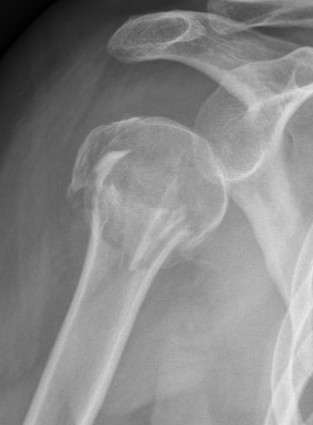

Avascular necrosis

- avascular necrosis 5%